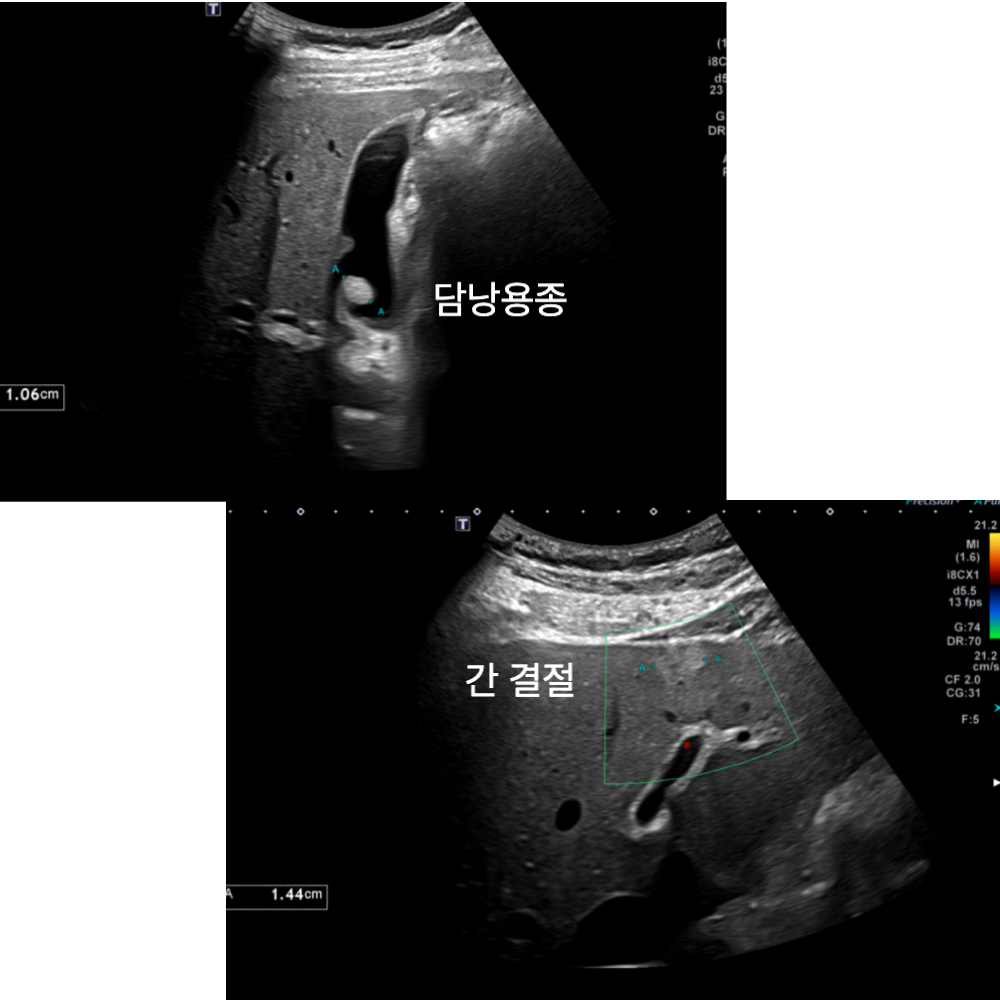

초음파: 지방간, 1cm 크기의 담낭용종, 간 결절 발견, CT: 1.4cm 크기의 간혈관종 확인(양성) → 정기 추적 계획.

• 복부초음파: 담낭용종과 간 결절 확인 복부초음파: 담낭용종과 간 결절 확인